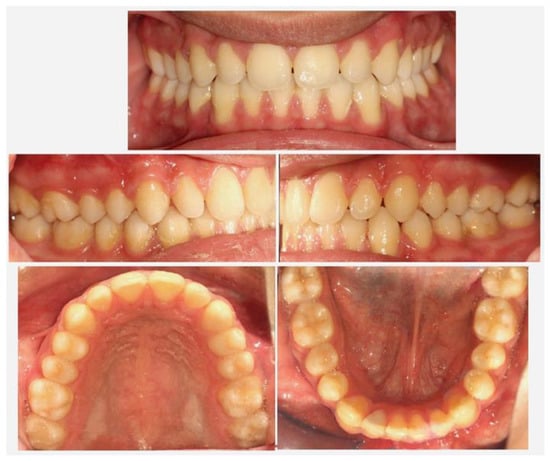

2. Materials and Methods

3. Results